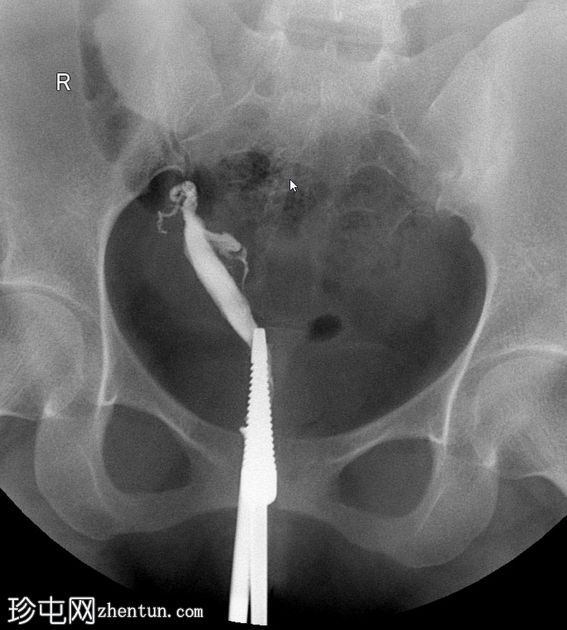

子宫输卵管造影

正位

1.jpeg

子宫输卵管造影显示两个独立的子宫腔,完全重复。可见两条独立的宫颈管。每个子宫角分别与其对应的输卵管相通。无统一的子宫底;子宫角明显分离。两个子宫腔均充盈并溢入腹腔。